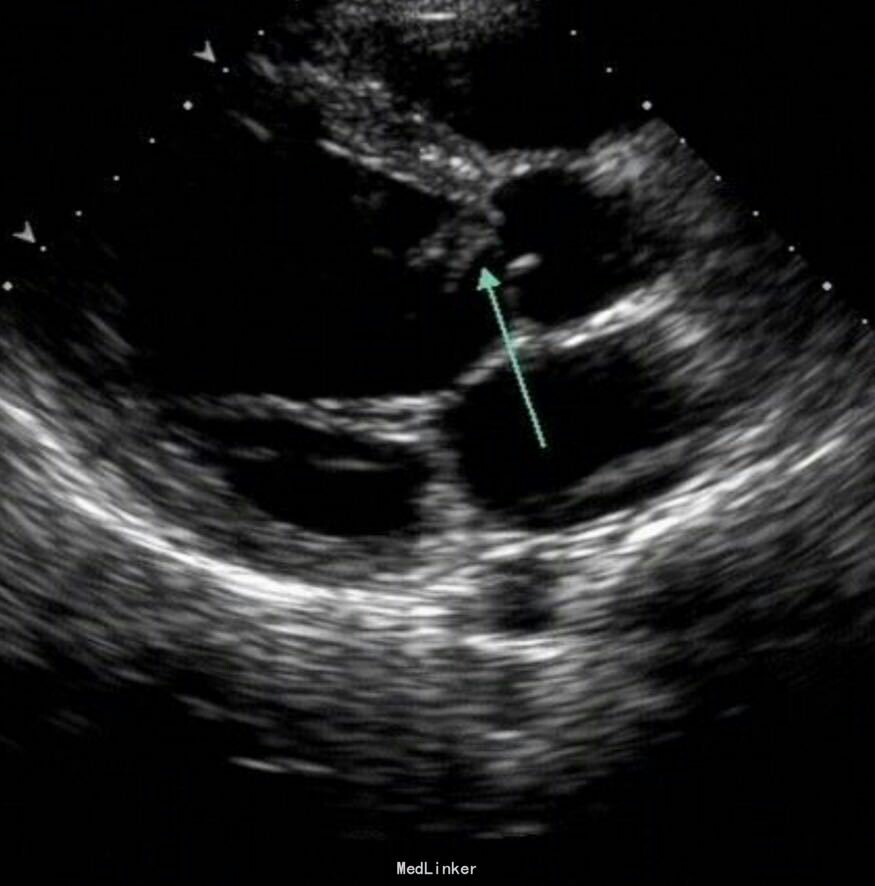

患儿男,13岁,因发热10余天,左下肢疼痛1天入院。查体:跛行,营养欠佳,左下肢活动受限,可见散在淤点,胸骨左缘2-3肋间可闻及舒张期杂音。左小腿有触痛,无肿胀,皮温正常,胫后动脉搏动消失。辅查:血沉增快,CRP升高,血常规、凝血未见异常。行心脏超声提示二尖瓣赘生物,下肢浅表静脉发现实质性回声,结合患儿有发热病史,进一步行血培养为阴性。诊断:感染性心内膜炎。予静滴头孢曲松抗感染治疗,同时予华法林抗凝。一周后患儿仍有发热,考虑金葡菌可能大,更换万古霉素抗感染。治疗10天后仍有发热,转外科行手术治疗。